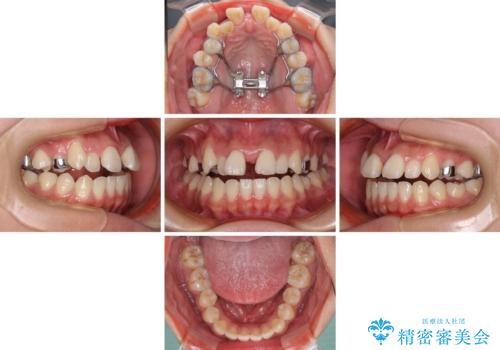

- 前歯の開咬と、上顎前歯の八重歯やデコボコを気にして来院された患者様です。

上顎歯列が狭窄していたため、急速拡大装置により上顎骨を側方に拡大し、その後ワイヤー装置にて矯正治療を行うこととしました。